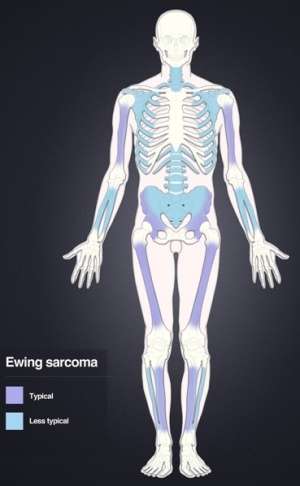

Distribution of Ewing's sarcoma: Most frequent locations are the large long bones and the pelvis.

- Most often found in pelvis, axial skeleton, or diaphysis of femur with a small minority arising in soft tissues